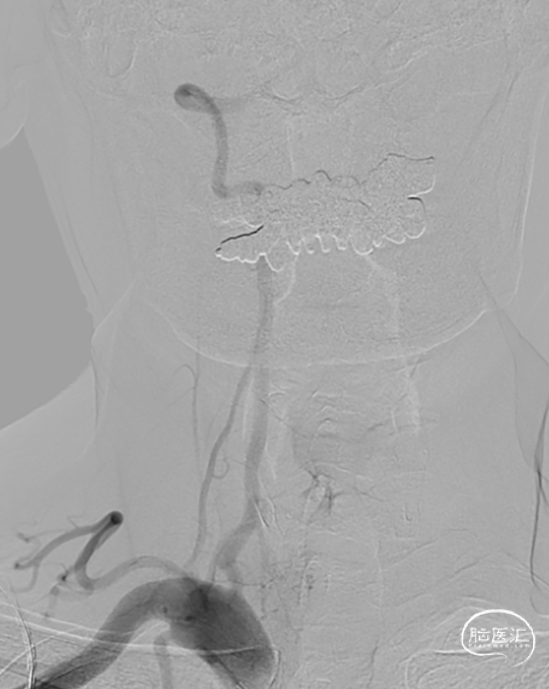

DSA示双侧椎动脉V4段狭窄,右侧为著且合并梭形动脉瘤。

术前DSA。